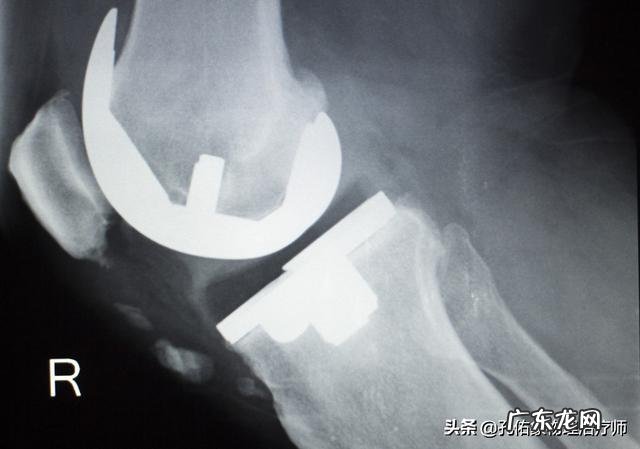

半月板损伤,若是不注意zhi疗,或是zhi疗方法选择不当,会有什么样的后果?对于严重的半月板损伤,症状也比较明显,甚则会有积液,日常活动受限,急性期后,若是还想着需要跑步,或是过多高负荷的活动膝关节 。那么您的膝关节注定不会好,可能以后经常会出现疼痛,活动的时候有弹响声,甚至还会出现弯伸小腿的时候有交锁感,长期下去,就是膝关节提前退变,出现骨关节炎,最终就是膝关节的人工假体置换 。